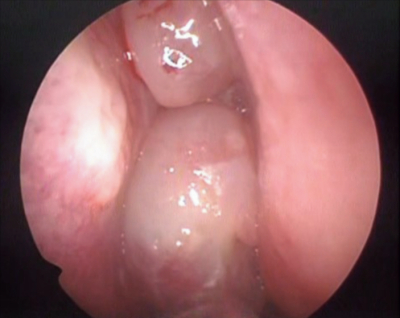

48 歳の女性。鼻閉を主訴に来院した。数年前から鼻閉と嗅覚低下があり、風邪をひくと悪化した。鎮痛薬で気管支喘息を起こしたことがあった。左鼻腔の内視鏡像を別に示す。右鼻腔も同様の所見である。副鼻腔単純 CT の水平断像と冠状断像を別に示す。

慢性副鼻腔炎の症例。

内視鏡下鼻副鼻腔手術は、慢性副鼻腔炎や鼻茸に対して広く行われる治療法で、症状の改善と機能の回復を目的としている。

内視鏡を使用することで副鼻腔内の病変に直接アクセスし、鼻茸の除去や排液の改善を行う。